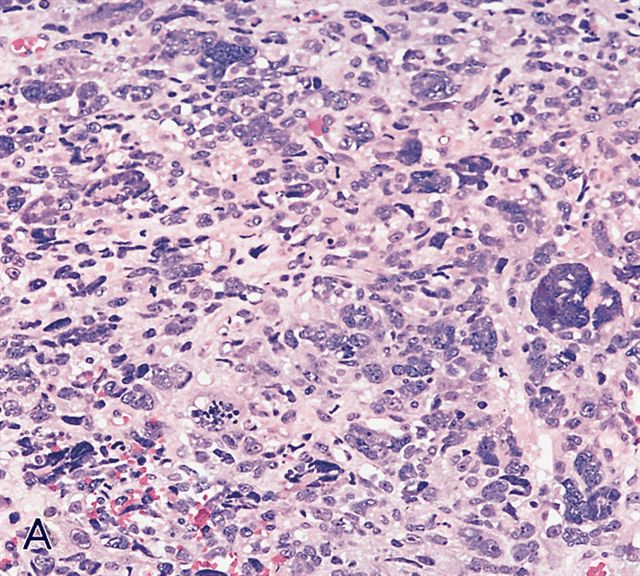

Contributed by Erdener Özer, M.D., Ph.D. and Mark R. Wick, M.D.

AFIP images - anaplastic rhabdomyosarcoma

Microscopic (histologic) description

- Composed of primitive mesenchymal cells that show variable degrees of skeletal muscle differentiation

- They are moderately cellular but in the typical pattern often contain both hypocellularity and hypercellular areas with a loose, myxoid stroma

- Perivascular condensations of tumor cells in the less cellular regions are common

- Sheets of small, stellate, spindled or round cells with scant or deeply eosinophilic cytoplasm and eccentric, small oval nuclei with a light chromatin pattern and inconspicuous nucleoli

- Can occasionally identify tumor cells that contain generous amounts of eosinophilic cytoplasm, a feature of rhabdomyoblastic differentiation (so called strap cells)

- May have cells with elongated tails of cytoplasm (tadpole cells)

- Cells are undifferentiated, round or spindled with minimal cytoplasm, frequent mitotic figures

- Anaplasia is defined similar to anaplastic Wilms tumor as a significant nuclear variation (cells that are 3x larger than background tumor cells) and the presence of atypical multipolar mitotic figures